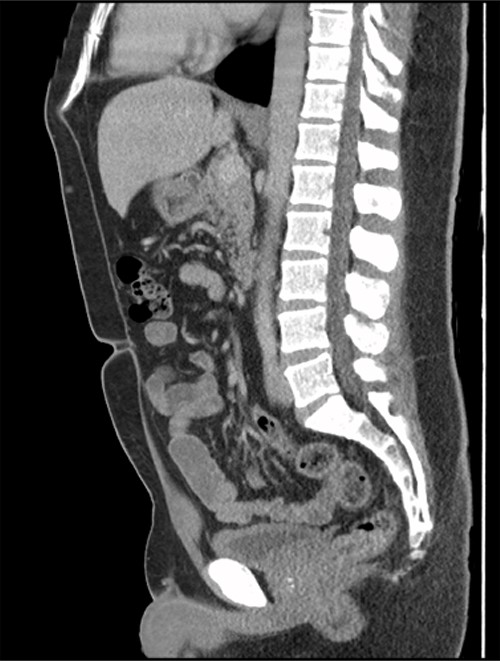

The patient had an uneventful recovery post operation. A retrospective review of the patient’s previous imaging revealed evidence of an appendicolith at the time of appendicitis diagnosis (Fig. 4). Despite the presence of the appendicolith on the preoperative CT, the histology of the resected appendix did not describe the presence of the imaged appendicolith. In addition, there was no evidence of a urachal lesion then on the initial imaging (Fig. 5), nor was there an intraoperative report of abdominal abnormalities during the appendicectomy. Therefore, it is hypothesized that the urachal lesion was an abscess secondary to the retained appendicolith from the appendicectomy.

Axial CT image. Arrow indicates appendicolith present within the appendix, with minor fat stranding surrounding the appendix.